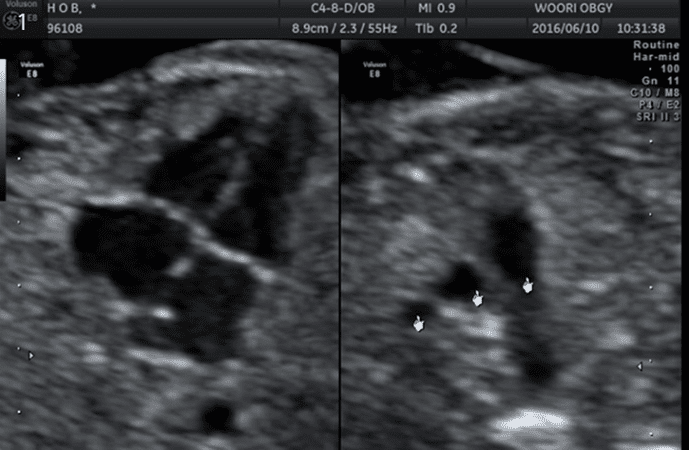

정밀초음파검사

태아의 기형을 진단하는 기본 초음파 검사이며 예약이 필요합니다. 임신 18-23주 사이에 태아의 장기를 세밀히 관찰하여 태아의 기형 유무를 확인하여, 출산 시 심한 기형으로 위급한 상황을 초래할 수 있는 태아(2-3%)를 진단하는 것이 목적입니다.